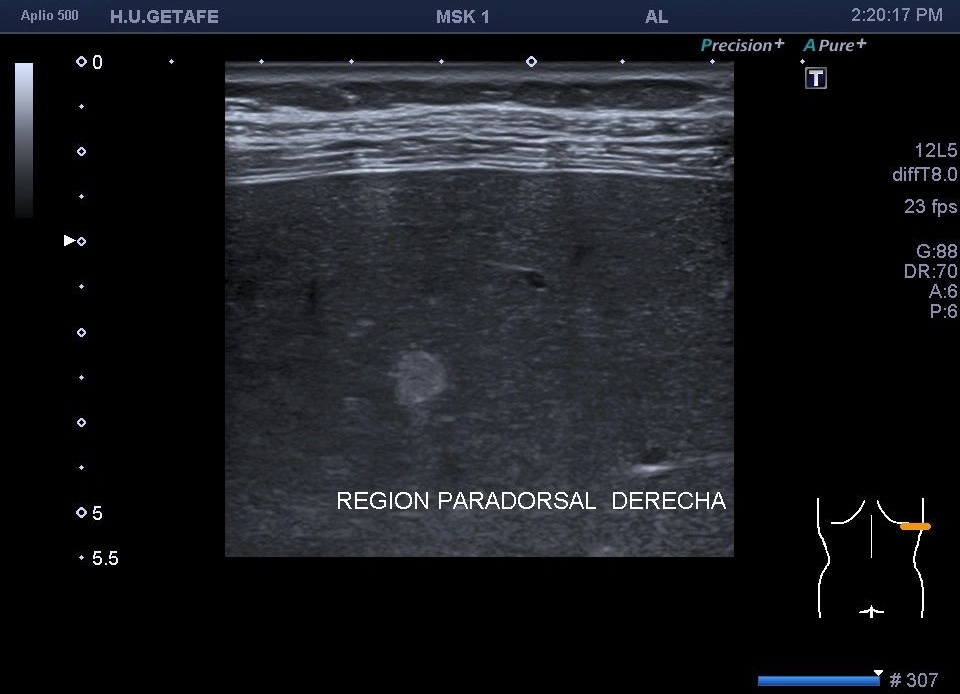

329. Hemangioma hepático. Vista con Sonda lineal.

Hiperecogénicas, redondas u ovaladas, de brillo variable, menores de 3 cms.

Pero en esta ocasión te quiero mostrar una cosa muy a tener en cuenta. En este caso es un estudio muscular dorsal y como hallazgo casual encontramos un montón de micro hemangiomas todos menores de 5 mm y que se hacen visibles por el uso de la sonda lineal de alta frecuencia.